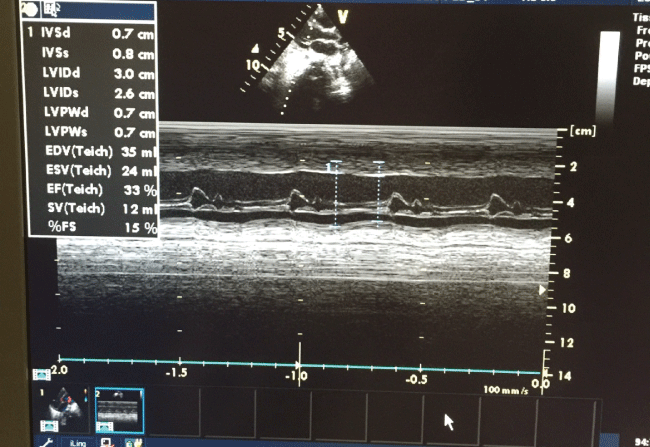

Initial ECHO showed severe left ventricular dysfunction with poor contractility, with dilated right ventricle, myocarditis, moderate mitral and tricuspid regurge, FS 14% (Figure 2a). Three weeks later, Myocarditis was improved with normal heart function. FS 38%. Six months follow up showed normal left ventricle function, no mitral regurge, FS 32%, EF 63% (Figure 2b).